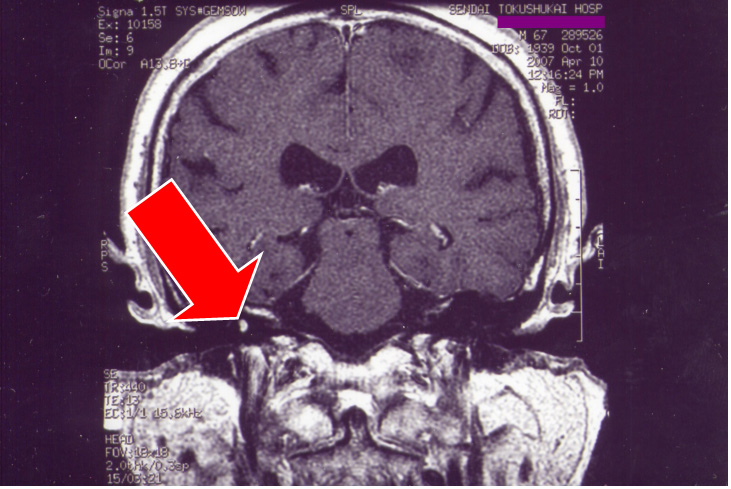

次にMRI画像(図12、13)を示すが、矢印が右側前庭内神経鞘腫である。

図12 図13